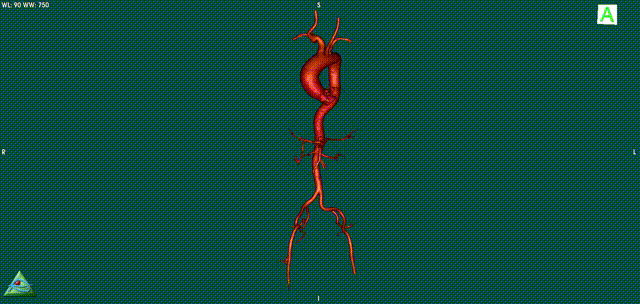

近日,中国医科大学附属盛京医院心脏内科庞文跃主任团队成功完成一例高难度复杂的TAVR病例。庞文跃主任团队经过术前的精准评估,发现患者左冠闭塞风险高、横位心、Type1型二叶瓣。通过术中紧密配合应用“snare技术”和“烟囱技术”,加上plus系统可回收再定位功能,顺利植入TAVR瓣膜,术后血流动力学有效改善,手术取得圆满成功!

左冠风险评估

26VenusAplus+snare

瓣膜内22mm球囊后扩张,左冠无显影

LM烟囱支架植入4.0*30mm